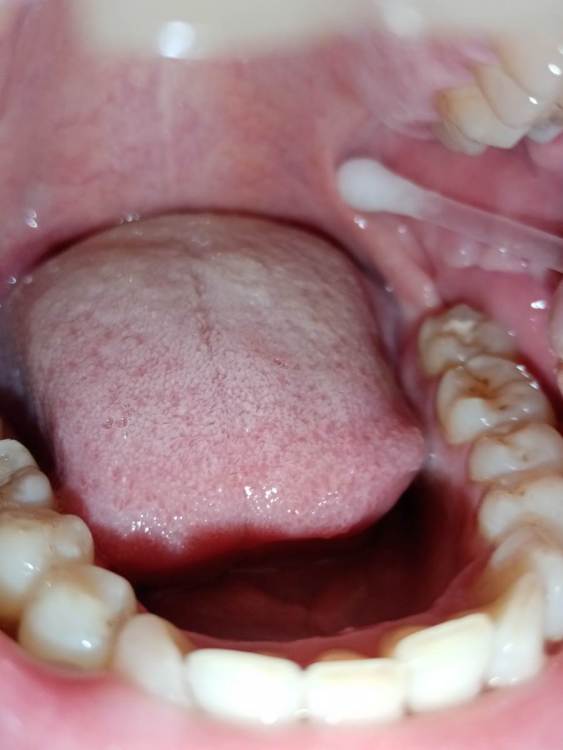

СмирноваД Опубликовано 29 июня, 2023 Поделиться Опубликовано 29 июня, 2023 Уважаемые стоматологи. Прошу Вашей помощи в поиске проблемы. Зуб удалили 2 года назад, но покоя там слизистая не дает. Болит, Разговаривать не дает вообще. Как буд-то там все пришили, и щеку и тяж со стороны горла. Какая-то шишка растет в конце верхней челюсти и как-будто давит там. Срослось оно вот таким образом "V"(со слов врача). Дергает щеку сильно , как-будто она прям пытается оторваться оттуда. и при наклоне головы прям в это место отдает. Со стороны горла тяж пришитый прям лоскутом к челюсти со стороны языка, трется об язык и тянет так сильно, что не дает разговаривать вообще, больно любые напряжения(разговаривать, глотать, пить,смеяться, и т.д.) прям чувствую как оно там все двигается, как нахождении чего-то инородного. Постоянно там все полощу, держу воду, потому что жжёт сильно. И доходит до рвотного рефлекса. Со стороны щеки,за зубом 4.7 корман. Пища попадает , и вытащить ее проблематично. Постоянно ощущение воспаления и лазию туда языком отодвигаю этот тяж, засовываю туда ватный диск, что бы просто снять напряжение и в этот момент могут быть такие жутки спазмы, что замираешь от боли. До трясучки и панических атак уже. Прикусываю там все, при чом даже с шиной (сплинт), щека лезет между зубов, приходится щеку вытаскивать.Шину ношу уже 10 месяцев, а толку нет. Рефлекторно, стараешься не двигать просто правой стороной вообще. Гнатолог , который делал шину, сказал, что нужно убирать рубцы, они все тянут. Но когда дошло дело до хирурга, хирург развел руками и сказал жить так, т.к. он ни чего сделать не может. Мало того у меня проблемы с суставом. а из-за этого напряжения на столько хуже, что к вечеру ни то что бы разговаривать, я и глотать слюну не могу. Сустав у меня теперь болит постоянно от напряжения, жуткие спазмы по всей голове, челюсти, до горла болит, с переходом на шею. При чом все врачи видят эти рубцы, что все прикусываю, трогают и мне больно, но говорят все по разному : один- надо искать, другой - там воспаление, третий- прикус, четвертый -как вы себе представляете это, это нужно было убирать сразу, пятый-сустав. Просто как идти к ортодонту с такими болями? И так же искала врача по пластике, но безрезультатно. На кт и снимках нет ни чего. Помогите, пожалуйста, хоть как-то разобраться. 230310_183333.rar Ссылка на комментарий

СмирноваД Опубликовано 11 августа, 2023 Автор Поделиться Опубликовано 11 августа, 2023 27.07.2023 в 19:43, annda сказал: Нельзя на ортодонтию идти в таком состоянии. Начните с банальной рутинной ежедневной самокоррекции хотя бы-пилатес,йога, Фельденкрайз и прочие подобные штуки. Единственные рубцы,которые у вас есть-это «линия Альба»,,следы прикусывания щек зубами.К месту удаления это не имеет никакого отношения, а к бруксизму -самое прямое. Извинете, Вы, не правы!Линия альбы! Тут ни какого отношения не имеет. Я не могу сфотографировать как выглядет вся слизистая за 4.7. зубом. Ссылка на комментарий

Bier Опубликовано 16 августа, 2023 Поделиться Опубликовано 16 августа, 2023 я вижу рубец на щеке, вы накусали его, ну если он мешает можно его отрезать. Но по источнику боли соглашусь с Анной. Ссылка на комментарий